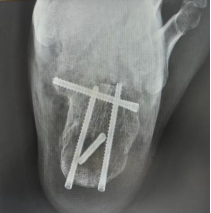

案例1:患者42岁,因高坠伤致左跟骨骨折、伴活动受限9小时入院。入院诊断:左跟骨骨折。入院后,科室采用3D打印导板辅助下行经皮跟骨骨折闭合复位内固定术,通过导入患者跟骨CT数据完成三维重建,在计算机上进行虚拟复位并精准规划出用于固定骨折块的最佳“虚拟螺钉”路径的进针点、角度及深度,以安全地穿过骨折块并达到最大把持力;再将计算机中的“虚拟路径”转移到患者体表,依据规划好的钉道,生成一个能与患者足跟外侧皮肤及骨骼解剖标志(如跟骨结节、腓骨远端等)完美贴合的个性化手术导板。术中只需将灭菌后的个性化导板准确贴合在患者足跟外侧预定的皮肤位置,借助导板导向孔直接钻入导针,实现了置钉精准化、手术微创化与效率提升的多重目标,最大程度保护了局部软组织血运,降低了伤口并发症风险。

(术中)

(术后)